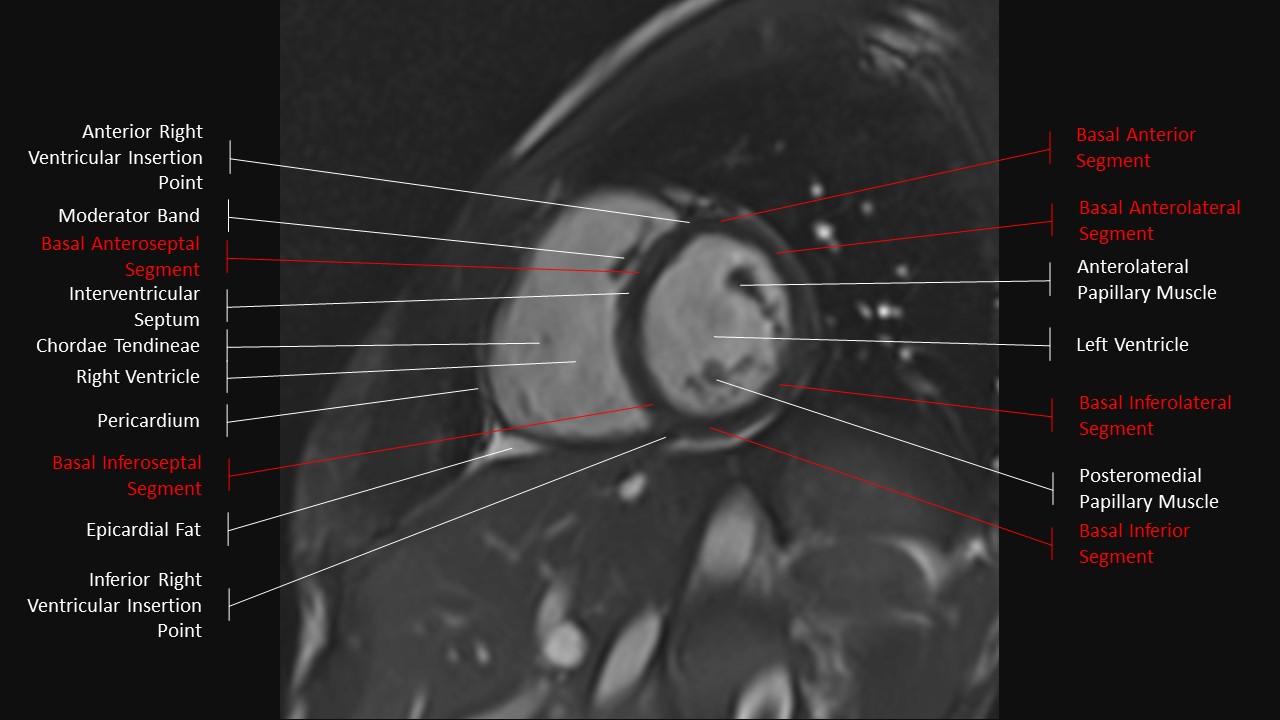

Short Axis Series